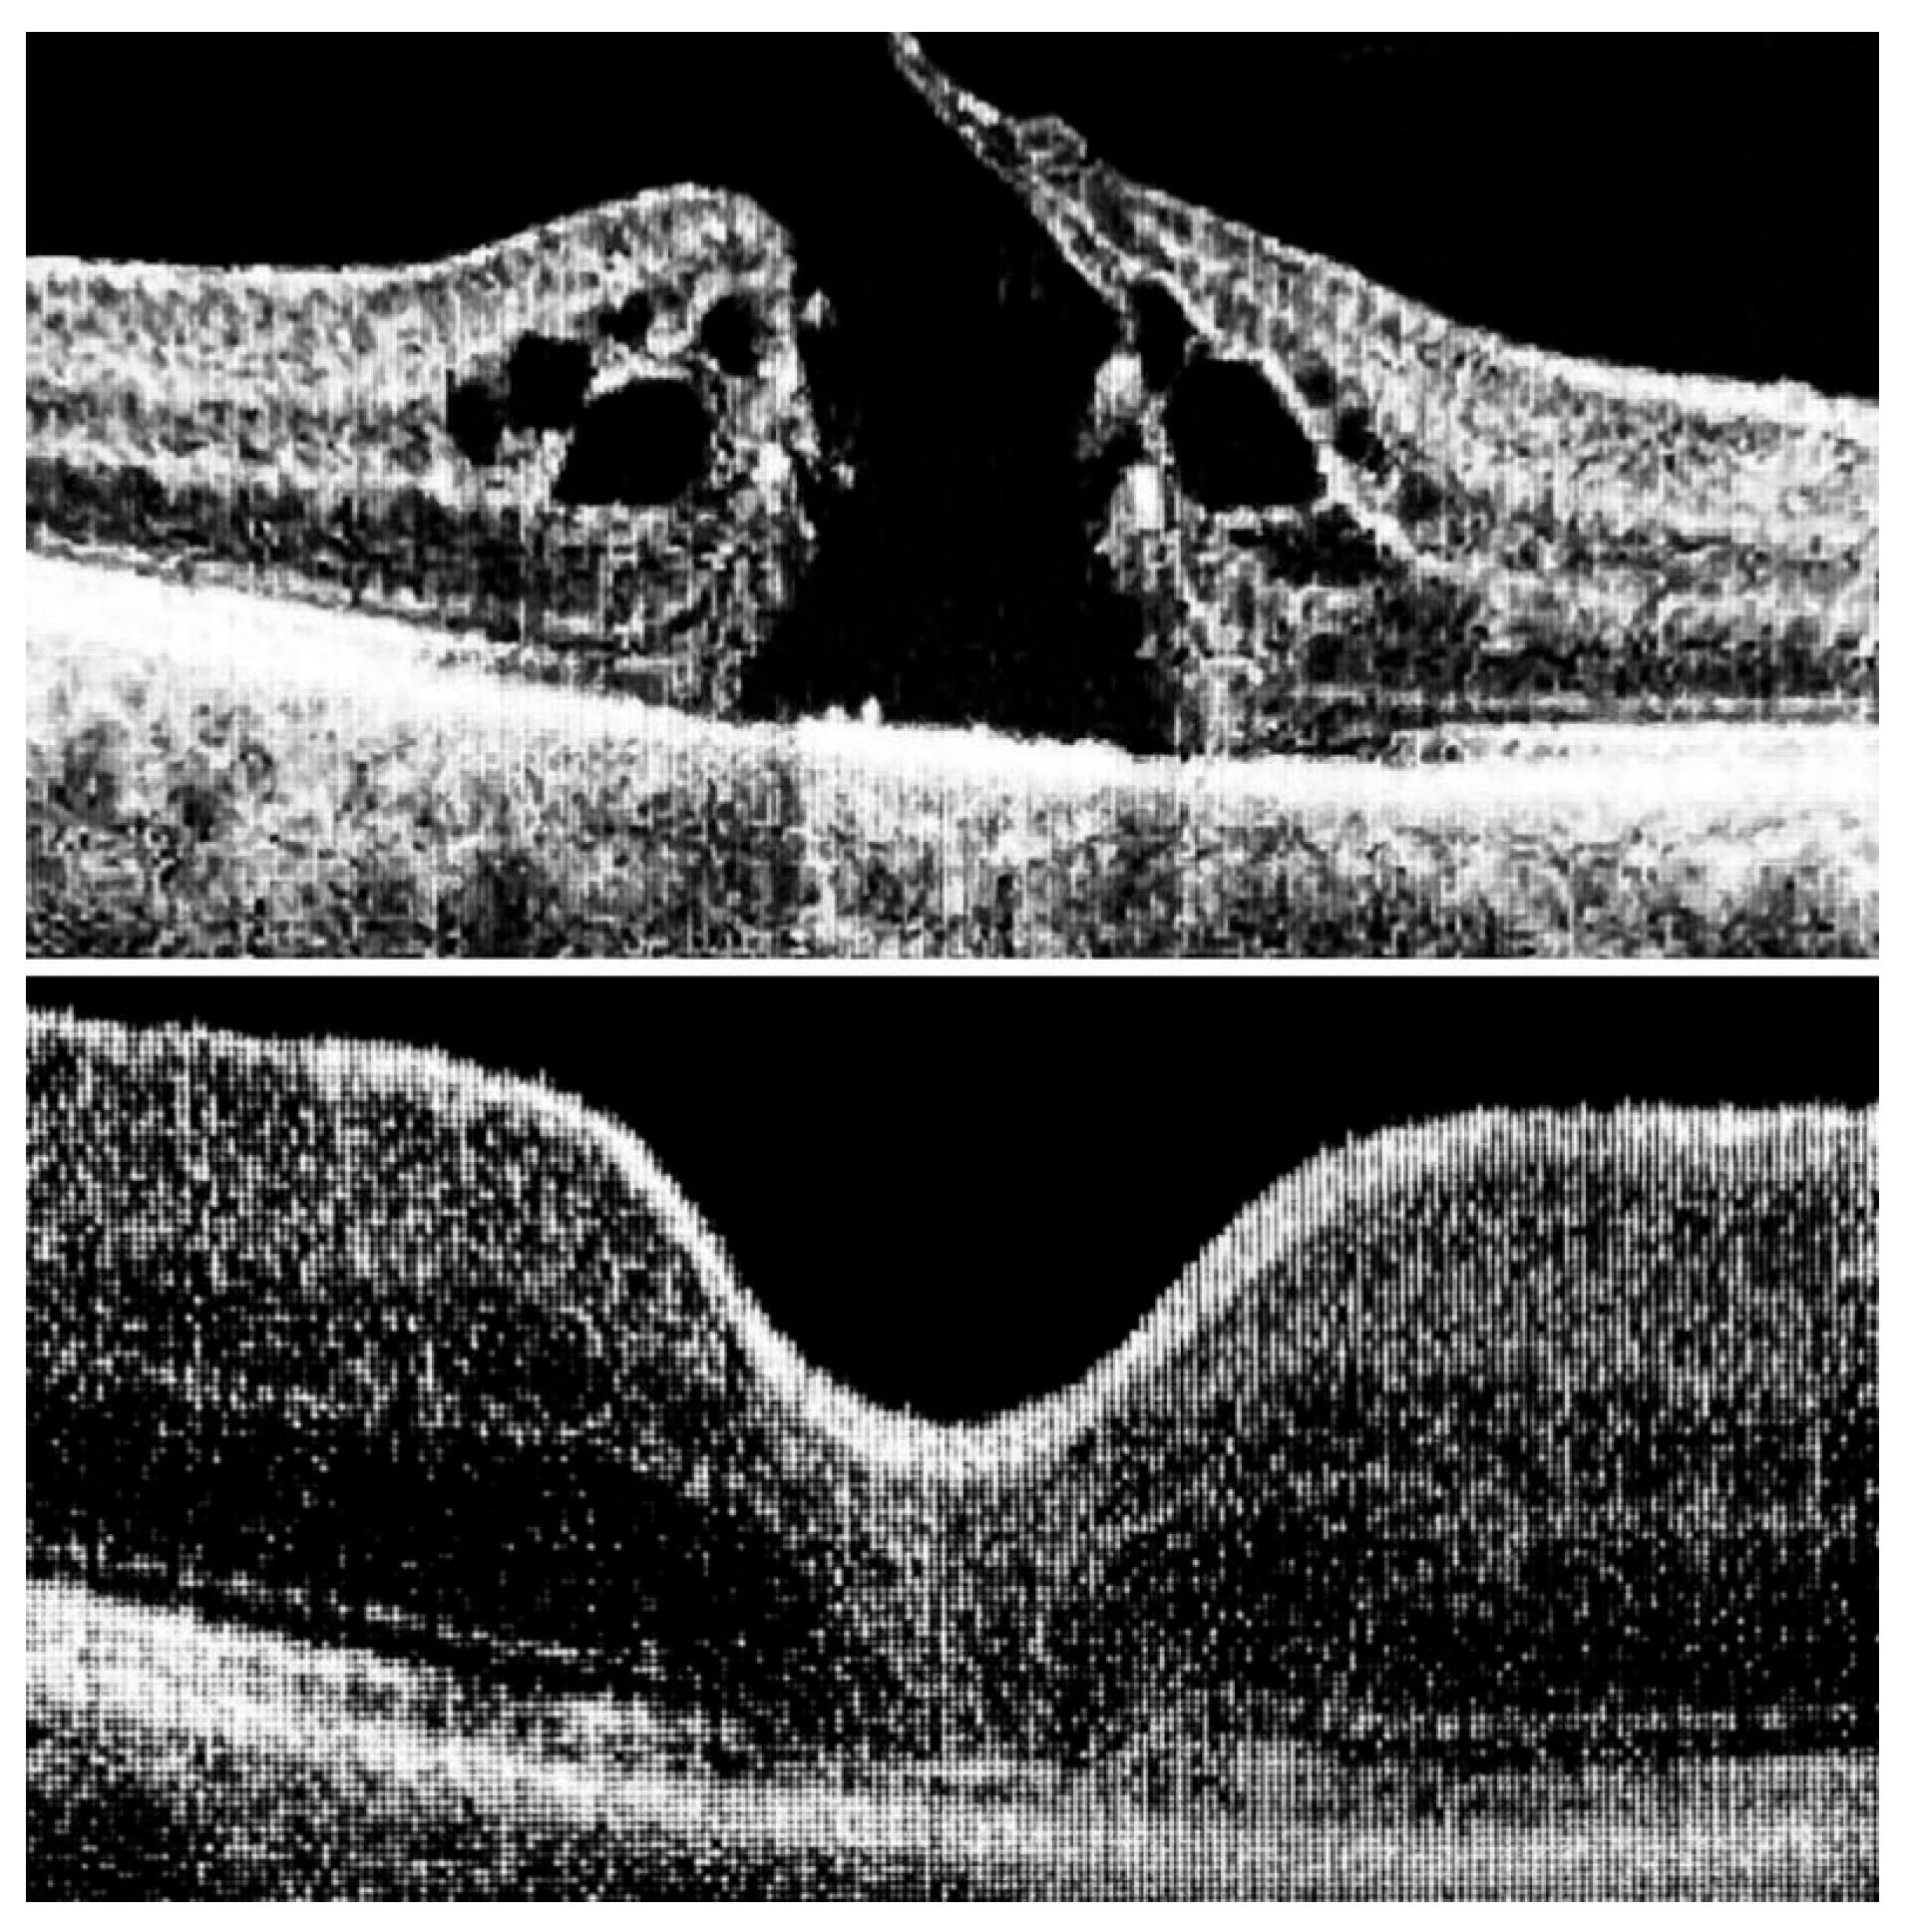

The ILM was peeled without the use of vital dyes, employing visualization techniques for transparent structures. A 25G silicone soft-tip cannula was used to gently approximate the edges of the macular hole under a balanced salt solution. Triamcinolone aceonide (Kenalog) was deposited on the ILM surface to enhance its visibility, and additional guidance was provided by instrument shadows under green-light illumination. Peeling was initiated at the point of weakest adhesion between the ILM and the retina. A pair of vitreoretinal forceps (e.g., Alcon Grieshaber AG, Schaffhausen, Switzerland) was used to gently grasp and lift the ILM to initiate separation. The extent of peeling covered an area of approximately 2–3 optic disc diameters around the hole to relieve tangential traction. Following ILM peeling and centripetal tissue mobilization, the macular hole edges were approximated under balanced salt solution or, in selected cases, perfluorocarbon liquid. Closure was monitored in real time using high-resolution intraoperative OCT (RESCAN™ 700 integrated with OPMI LUMERA® 700 microscope, Carl Zeiss Meditec AG, Jena, Germany). Representative intraoperative OCT images before and after ACP application are presented in Figure 1, Figure 2 and Figure 3.

Figure 3. At the top: long-standing macular hole persisting for 12 months; at the bottom: complete closure with restoration of all retinal layers, preserving ideal architecture and morphology, including the ninth layer—the retinal pigment epithelium (RPE).